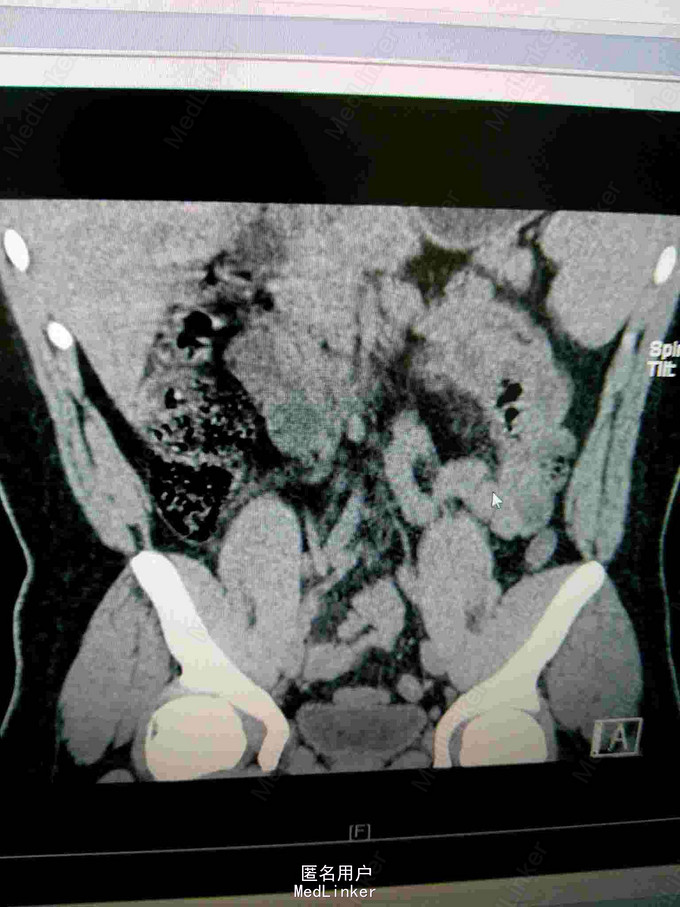

23岁男性患者,非洲加纳人,因"腹部疼痛半天"来院,现病史:患者半天前无明显诱因出现腹部疼痛,以下腹部持续性疼痛为主,阵发性加重,无发热,无呕吐,无腹胀腹泻,无尿频尿急尿痛等不适。患者有镰状细胞性贫血病史多年。

查体:神清,生命征平稳,急性痛苦面容,大汗淋淋,腹平,下腹部压痛明显,可疑反跳痛,无明显固定压痛点,上腹部轻度压痛,肝脾肋下未及,墨非氏征阴性,未及包块,双肾区无压痛扣击痛,输尿管行程无压痛,移动性 胞 浊音阴性,肠鸣音活跃。查血常规白细正常,中性正常,HGB95g/l,HCT26.7%,MC63.7fl,MCH22.7pg,MCHC356g/l,红细胞分布宽度差异23.7%,红细胞分布宽度标准53fl.淀粉酶正常。

镰状细胞性贫血并发肠绞痛。治疗:予补液,扩容,解痉止痛等对症处理。